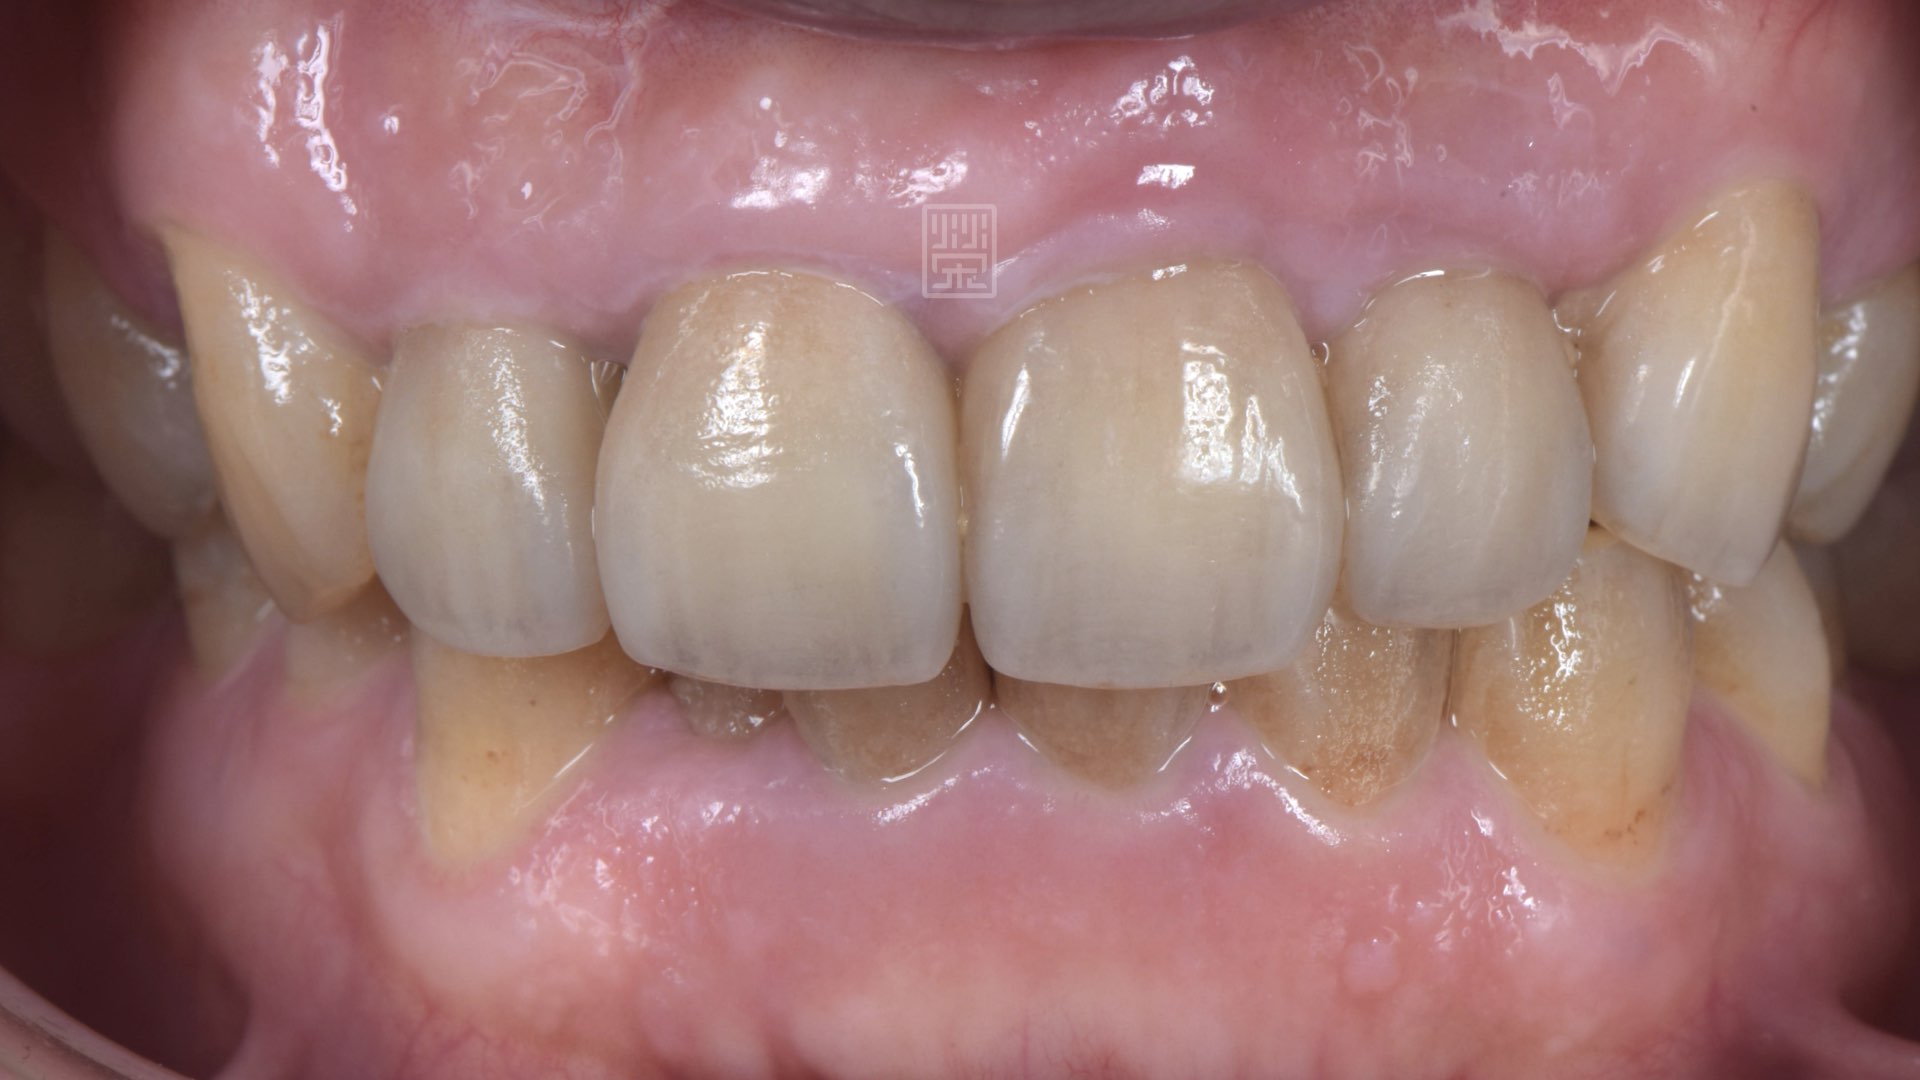

smile~~